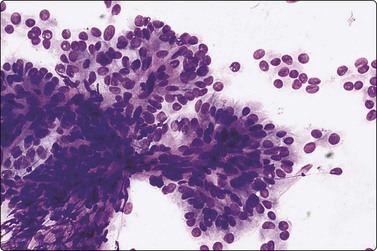

image image

Fig. 6.31 Comparison of sheets of papillary carcinoma and of macrofollicle in nodular goiter

(A) Papillary carcinoma. Flat sheet of epithelial cells; partly monolayered, partly with nuclear overlapping; uniformly enlarged, oval nuclei with pale powdery chromatin and small nucleoli; note ‘anatomical’ edge of a row of cells along upper edge (Pap, HP); (B) Nodular goiter. Flat monolayered sheet of cells from a disrupted macrofollicle; note frayed edges and uniformly small round nuclei (Pap, HP).

Smears in PC are cellular with numerous three-dimensional and papillary fragments (Fig. 6.30) with or without vascular cores. Often, papillae not removed intact by the needle appear as flat sheets. Sheets of cells show a distinct anatomical border, formed by a row of cuboidal or columnar cells (Fig 6.31A) with focal nuclear crowding and overlapping, features that distinguish sheets of PC from those representing benign macrofollicles (Fig. 6.31B). The tip of a papilla may be seen as a finger-like aggregate of cells with a similar edge (Figs 6.32 and 6.33A). Naked true papillary connective tissue cores are sometimes found and can be diagnostically helpful. Trabecular fragments (Fig. 6.33B) (also present in FN) are represented in smears by cohesive finger-like structures and must not be mistaken for papillae. Seventeen percent of cases show concentrically organized aggregates of tumor cells or ‘swirls’ (Fig. 6.34), the most peripherally located cells appearing ovoid with nuclei oriented perpendicular to the radius of the swirl.163 A few cases show only dispersed single cells and syncytial aggregates; diagnosis then relies on identification of nuclear features of PC.